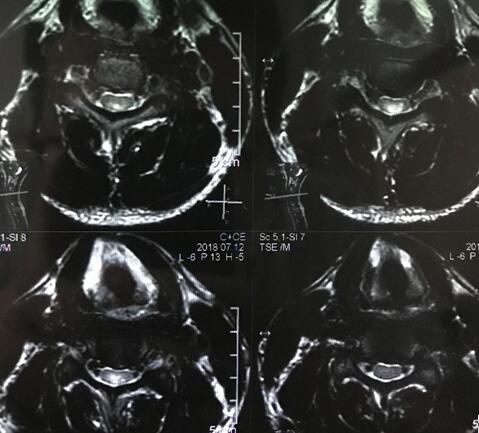

小张开始意识到自己情况的严重性,在家人的陪同下前往当地医院就诊。颈椎核磁共振显示,小张脊髓里有个异常信号,但不能明确诊断出这个异常信号究竟是什么疾病的表现。为寻找确切的治疗,小张辗转多家医院,结果仍然是不能明确这个信号代表的是何种疾病,陆陆续续的治疗也没有起到任何好转的效果。为了查明病因,小张慕名找到了我院神经内一科主任王展航。

作为广东省知名的神经内科专家,王展航对小张的病情非常重视,多次亲自对患者进行精细的神经专科查体。结合患者既往胃病史及外院核磁共振片显示的脊髓后索病灶,他提出“脊髓亚急性联合变性”的诊断意见, 并制定了详细的治疗计划。仅仅用药一周,小张就觉得肢体的麻木感有所缓解.病情明显好转后出院。